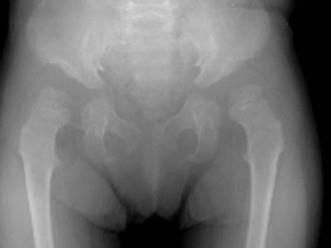

问题 女,3岁,身高不增,智力正常,请结合图像,选出最可能的诊断 ( )

选项 A、粘多糖贮积症I型 B、MPSII型 C、肾性骨病 D、粘多糖贮积症IV型 E、维生素D缺乏症

答案 D